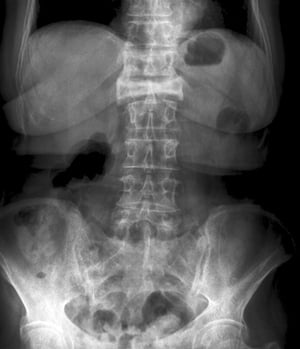

Questa frattura da compressione della 2a vertebra lombare è visibile come una perdita di altezza del corpo vertebrale sia nella proiezione antero-posteriore che laterale.

Scott Camazine/SCIENCE PHOTO LIBRARY